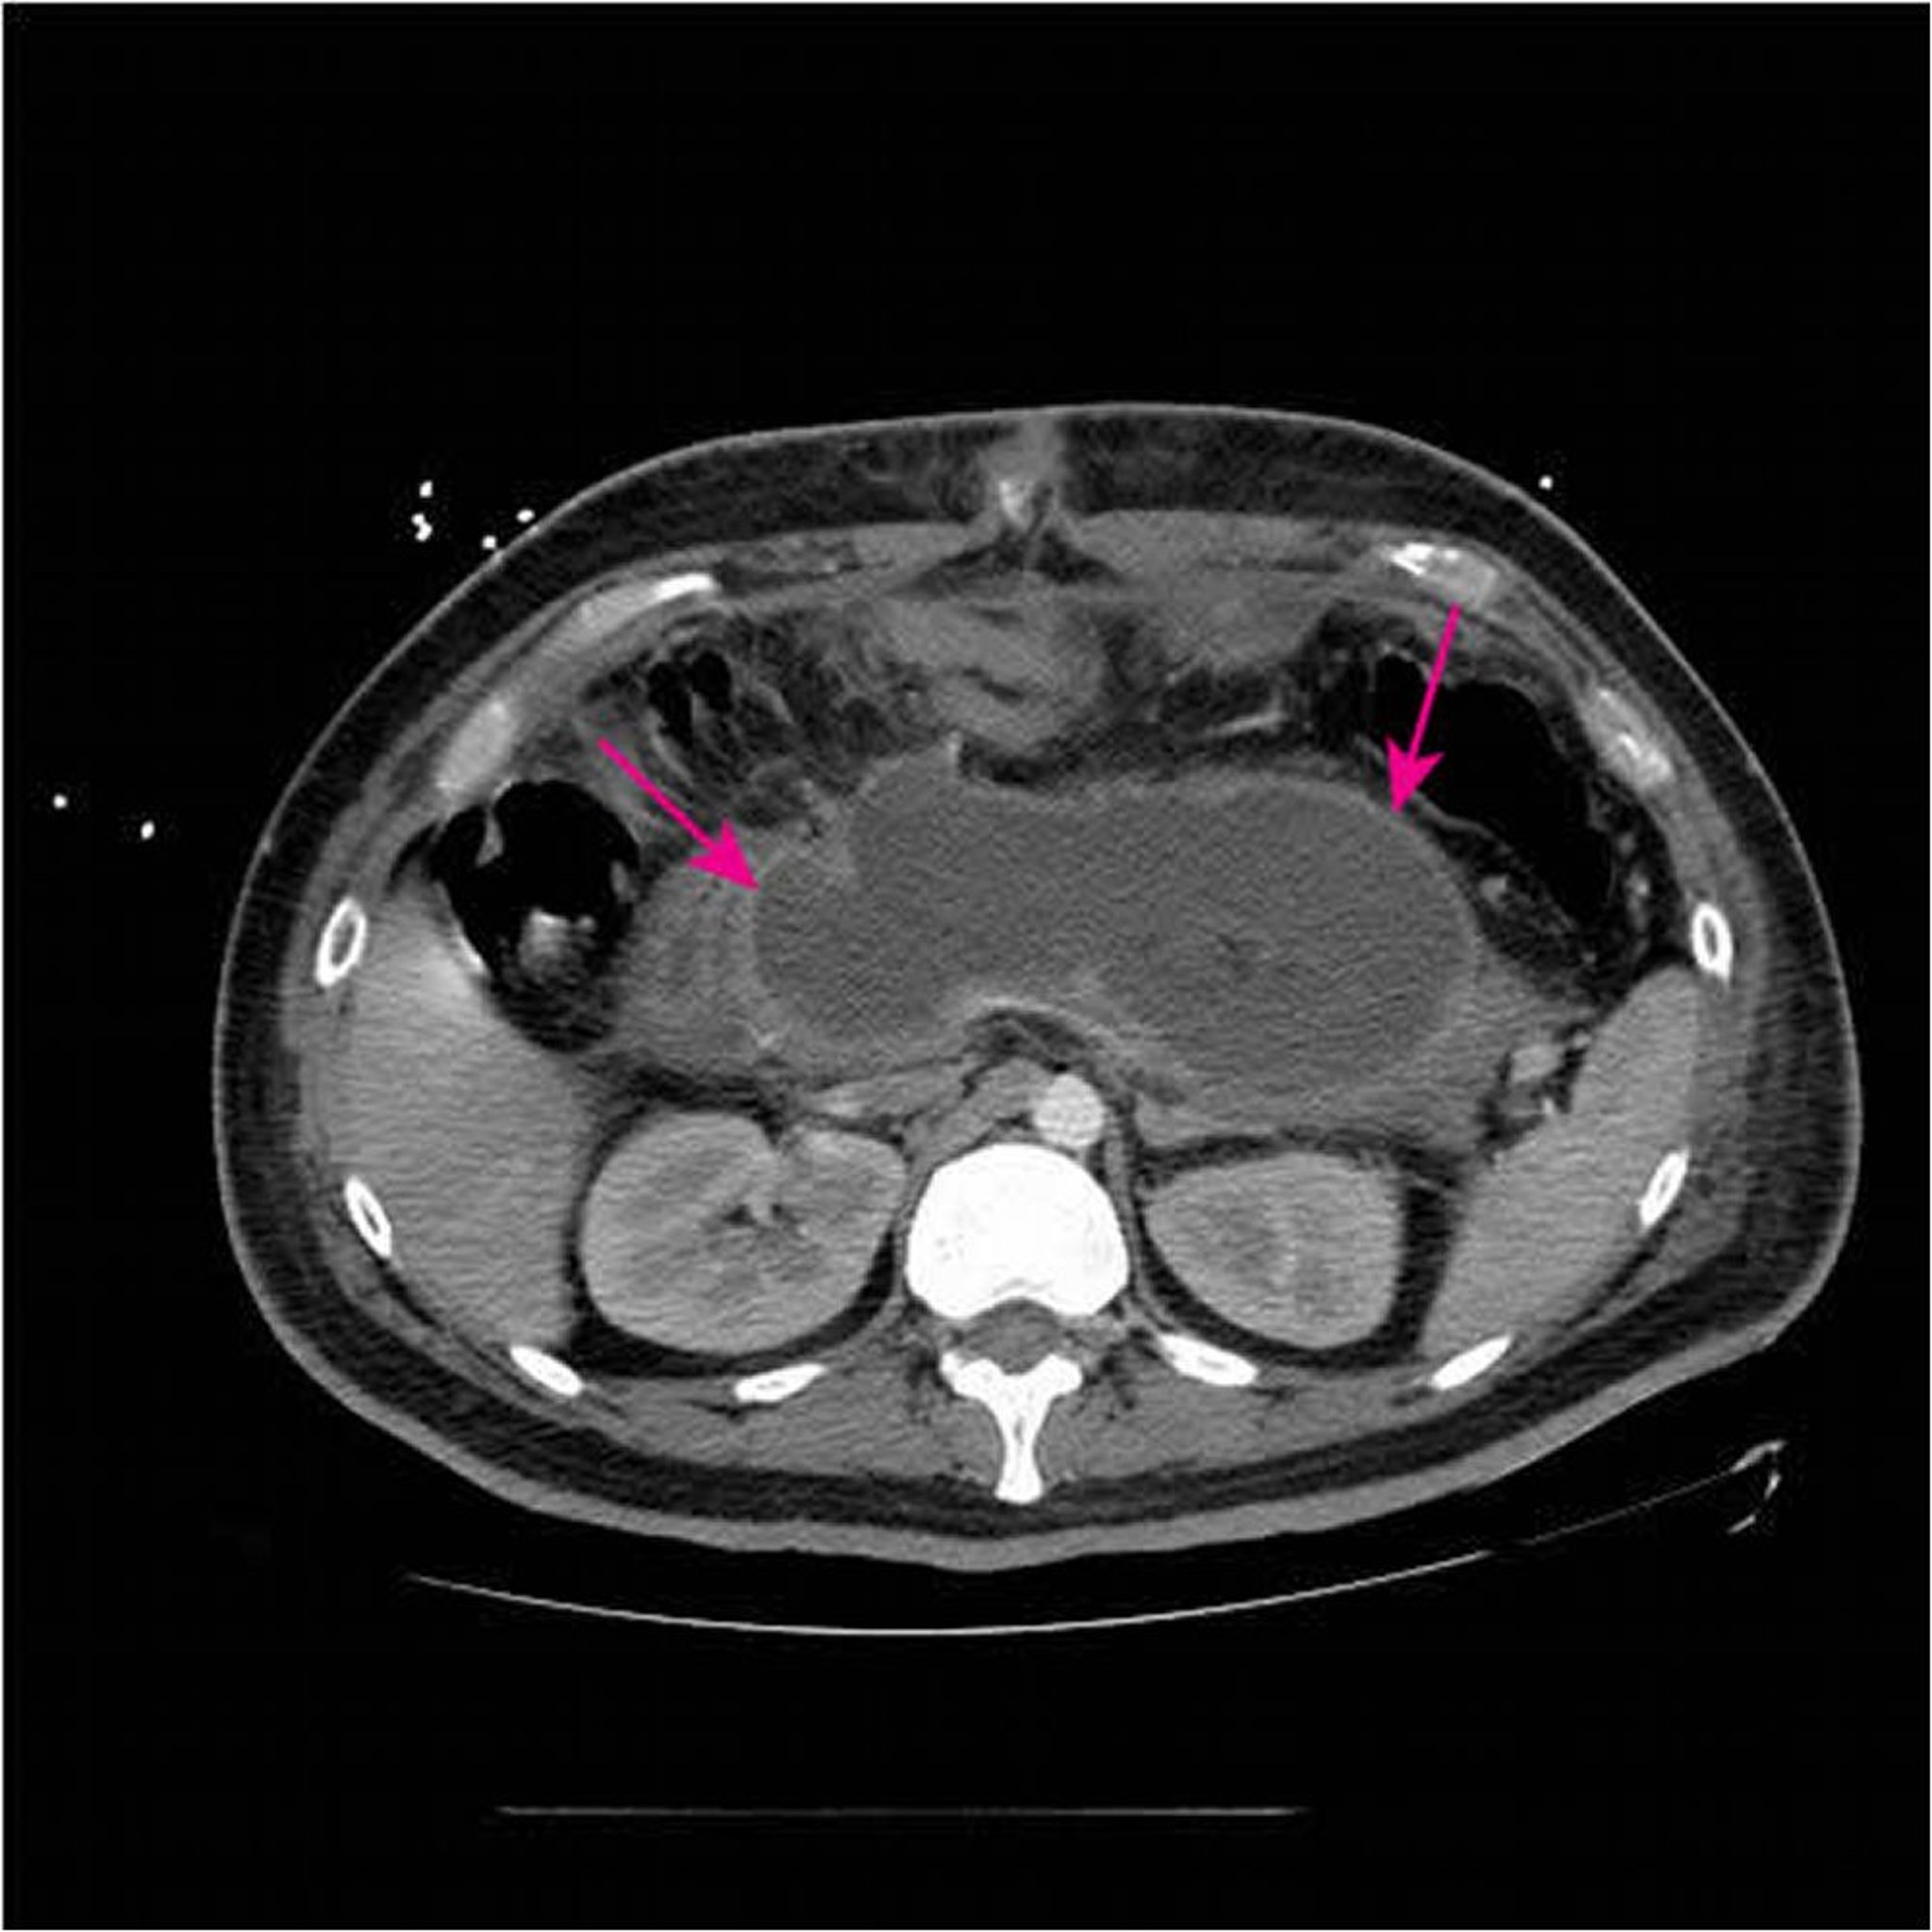

Colección necrosante aguda

Esta TC con contraste IV y oral muestra una gran colección necrosante aguda (flechas) que reemplaza la mayor parte del tejido pancreático < 4 semanas después de la presentación inicial de una pancreatitis necrosante.

Image courtesy of Sonam Rosberger, MD.